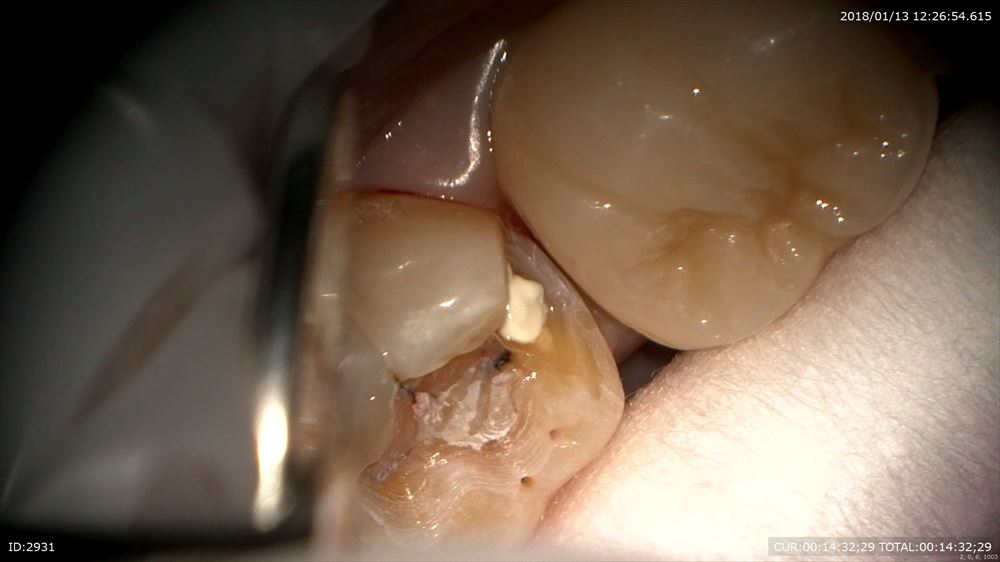

色々な人がきます。この方は他院で治療器具を残されたケース(根管治療に使う器具が根管の中で折れている)症状がなければまだ良いのですが。。症状があります。異物ですので確実に除去したい所です。今日は1時間半の格闘。超音波や色々な最新器具で隙間を器具と歯の間に作ります。0.1mmの世界。

光っているのが金属のリーマーです。

きたー。